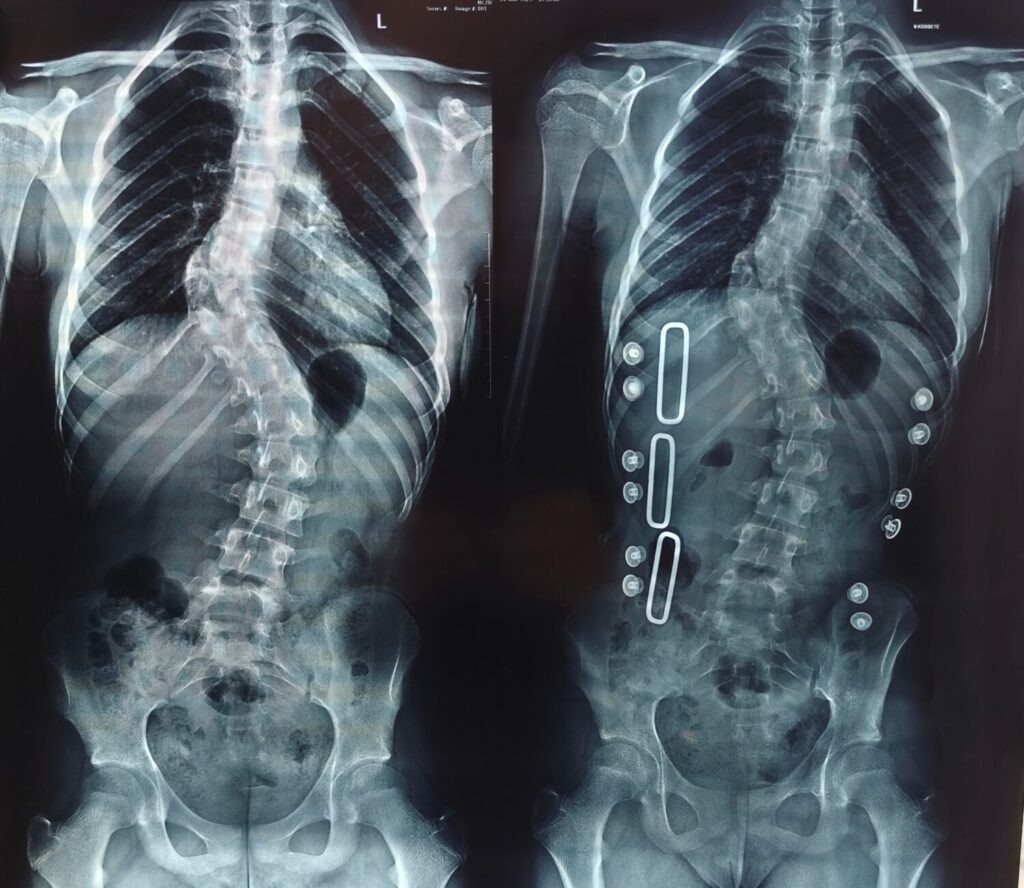

Недавно девочка опять была на приеме у врача, и ей снова сделали рентген. Результат изменений за год очень тревожный — искривление увеличилось на семь градусов. Это много — обычно сколиоз не прогрессирует так быстро. Надиря говорит: «Врач посмотрел наши результаты и сказал: "Корсет и зарядка не помогают, мучить девочку нет смысла, нужна операция. Срочно"».

— Нам рассказали, как будет проходить операция, — объясняет Надиря. — На позвоночник установят особую металлоконструкцию. Она содержит в себе шурупы, крюки. Ставится на позвоночник. Разрез делают сзади. С помощью такой конструкции деформация исправляется, и позвоночник фиксируется в правильном положении. Конструкцию удалять не надо, она остается на всю жизнь.

Так как Алия еще совсем юная и продолжает расти, ей нужна специальная подвижная металлоконструкция, растущая вместе со скелетом и позвоночником. К сожалению, по ОМС такая металлоконструкция не предоставляется. И девочке нужна наша помощь.